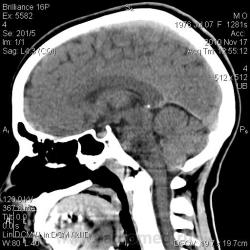

Тип патологии:

Область исследования:

Методы исследования: